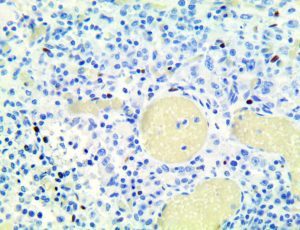

It is the ICU physician who is most likely to witness one of the deadliest manifestations of the abnormal immunological response, the cytokine storm syndrome (CSS). This response is also referred to by some as the cytokine release syndrome (CRS). CSS is characterized by continuous activation and expansion of macrophage and lymphocyte populations, which secrete large amounts of cytokines, causing the cytokine storm. This massive cytokine release is akin to hemophagocytic lymphohistiocytosis (HLH) disease, a syndrome characterized by initial unchecked and persistent activation of cytotoxic T lymphocytes and NK cells.

Clinical and laboratory manifestations of HLH include fever, enlarged liver and/or spleen, neurologic dysfunction, coagulopathy, liver dysfunction, cytopenias (i.e., low levels of erythrocytes, leukocytes, and/or platelets), hypertriglyceridemia, hyperferritinemia, hemophagocytosis, and eventually diminished NK cell activity as the immune system becomes progressively paralyzed. HLH can be familial (primary HLH) or secondary to another disease process (sHLH), such as rheumatic disease, in which it is referred to as macrophage activation syndrome (MAS, characterized by elevated ferritin).